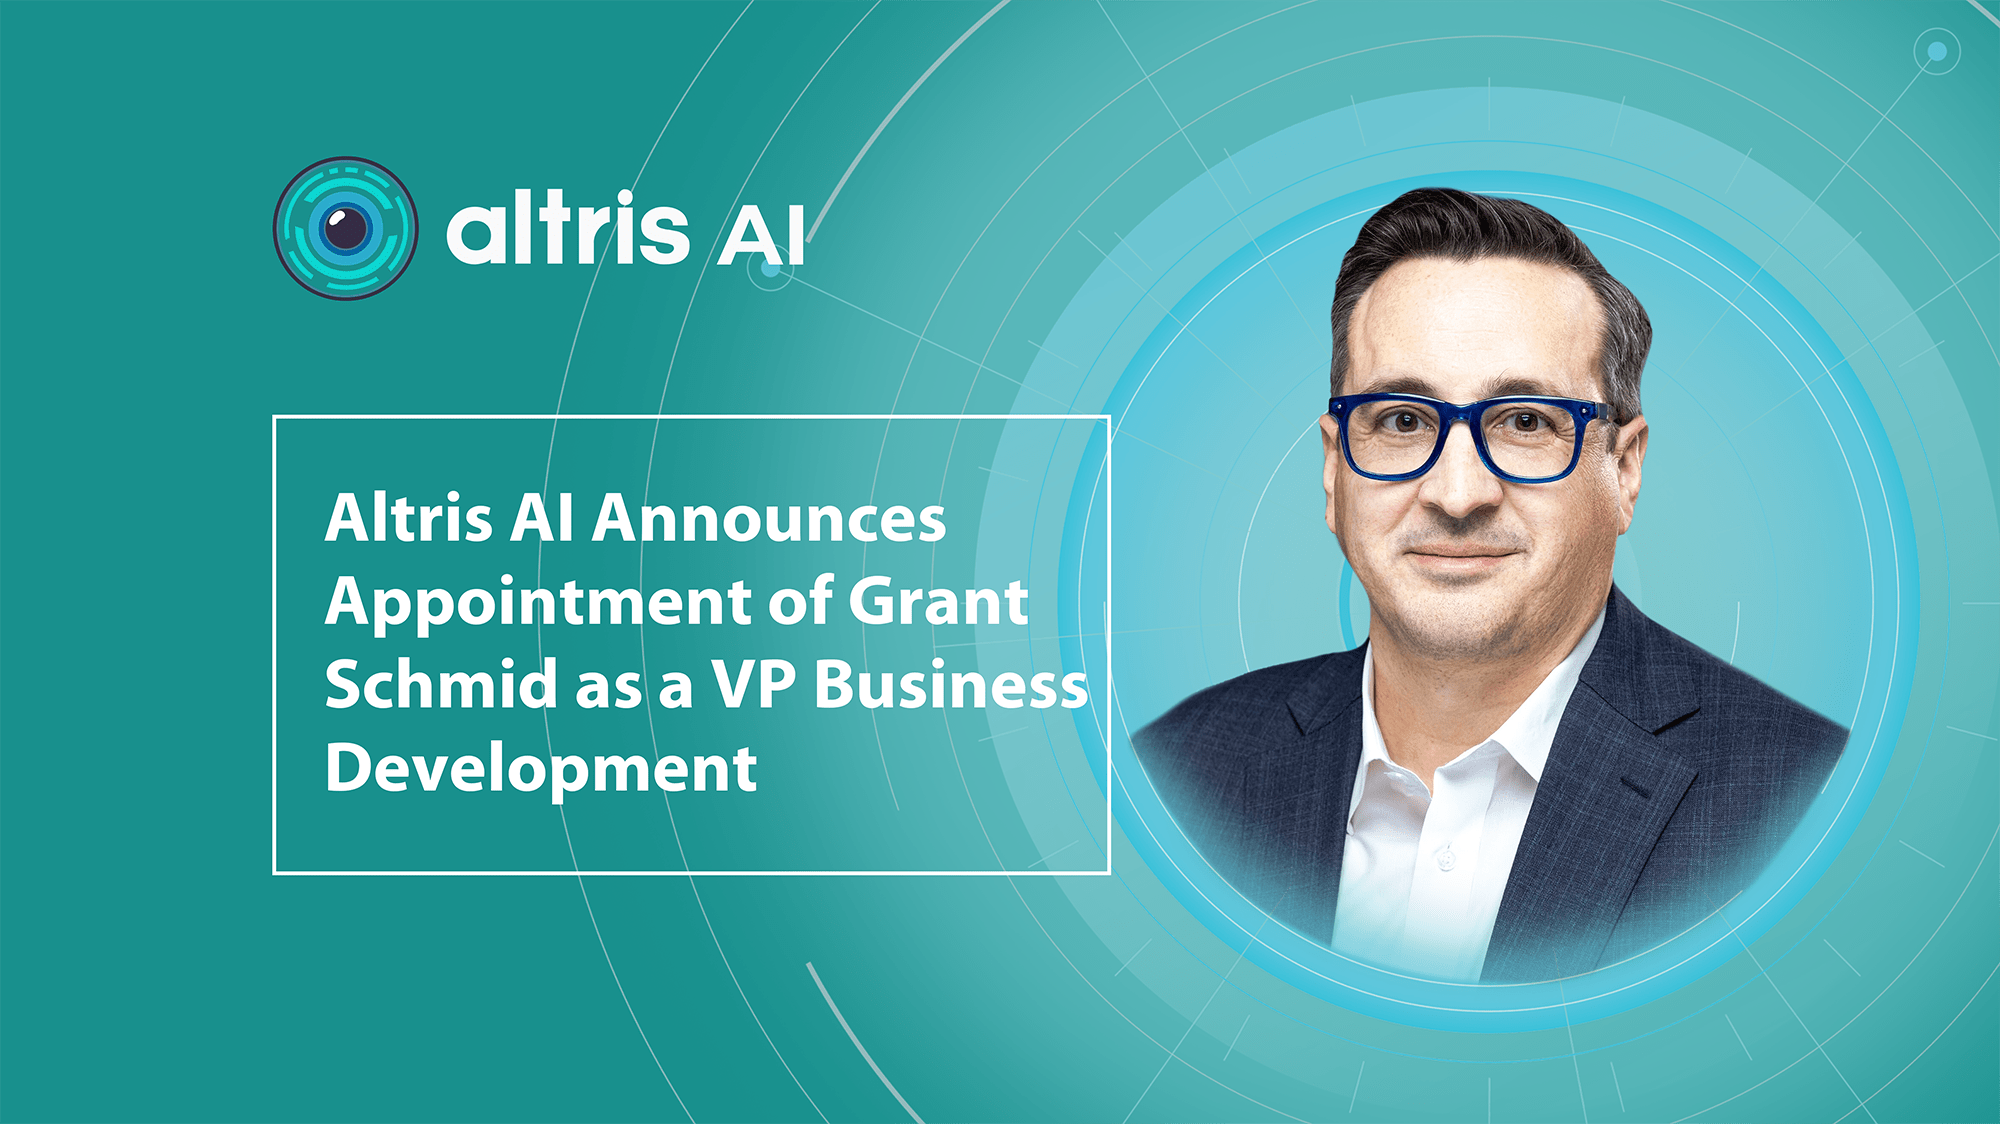

Altris Announces Appointment of Grant Schmid as a VP of Business Development

26.08.20241 min.Altris AI Announces the Appointment of Grant Schmid as the VP Business Development

Altris AI, a leading AI software provider for OCT scan analysis, announces the appointment of Grant Schmid as the Vice President Business Development. Mr. Schmid is a proven leader in the eye care industry and has solid experience that will help him establish new partnerships for the company and lead corporate sales.

The recent surge in AI (artificial intelligence) applications across industries has transformed the technology landscape, especially in healthcare. While AI companies have existed for years, the explosion of tools like ChatGPT has popularized the integration of AI in everyday processes.

Grant was drawn to Altris AI for its focus on harnessing AI capabilities to assist doctors in making faster and more informed decisions.

According to Mr. Schmid,

“Healthcare professionals are inundated with more data than most other professions, particularly in the eye care segment. Eye care specialists are subjected to multiple tests and instruments, generating a vast amount of data that must be reviewed comprehensively. A single Optical Coherence Tomography (OCT) test can contain over five hundred thousand data points. This necessitates that doctors carefully analyze results from various tests, often overlapping with different devices, which can be time-consuming and detract from the time they have with their patients.”

At Altris AI, the mission is not to replace the vital human connection in medicine but to enhance it.

Grant also remarked that,

“Some AI companies are positioning their products as replacements for human doctors, which undermines the essential aspects of patient care. Patients need to feel heard, and doctors choose this profession to help individuals. Altris AI enables doctors to spend more time with their patients, allowing them to focus on the human aspects of care rather than getting lost in data analysis.”

About Altris AI.

Altris AI is a part of the Altris Inc. ecosystem that includes Altris AI( a standalone AI platform for OCT scan analysis that improves diagnostic decision-making for eye care specialists) and Altris Education OCT (a free mobile app for OCT education interpretation). The mission of the company is to set higher diagnostic standards in the eye care industry and improve patient outcomes as a result. To achieve this mission the company created an AI-powered platform for OCT scan analysis that detects the biggest number of biomarkers and retina pathologies on the market today: 70 + including early glaucoma. More than that, the company offers an automated quantitative analysis of biomarkers and a progression analysis module for monitoring treatment results more efficiently.